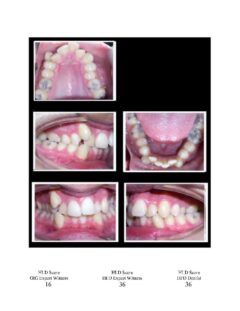

So here again are photos of children’s teeth that were pre-approved for treatment by the state’s Medicaid claims administrator TMHP/ACS, that HHSC-OIG now claims were fraudulently scored by Medicaid dental providers. These cases are from the SOAH hearings that have been completed for Harlingen Family Dentistry and Antoine Dental Center. The SOAH courts found both practices innocent of any allegation of Medicaid fraud or misrepresentation. The photo pages show the attending dentist’s HLD score, the dentist’s expert witness score and the OIG expert’s score.

Harlingen Family Dentistry